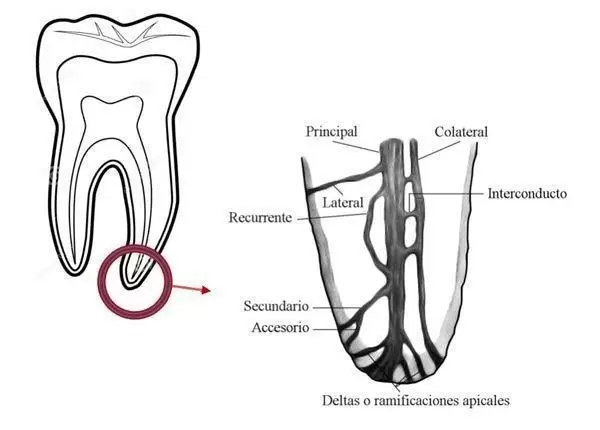

Según la anatomía dental de cada persona, la endodoncia puede tener más o menos posibilidades de éxito la primera vez que se realiza. La disparidad de conductos secundarios que puede tener la raíz de un diente hace que la tarea de eliminar el tejido infectado de los canales radiculares se complique y en ocasiones sea totalmente imposibilite.